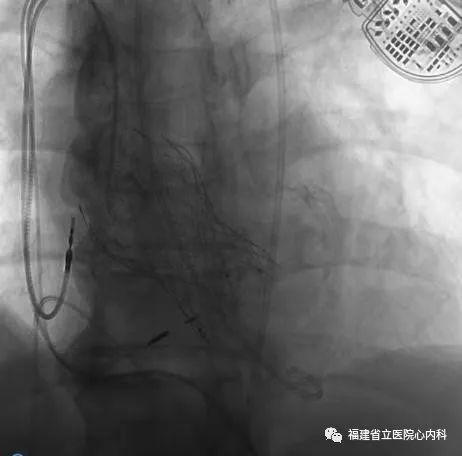

该病例主动脉瓣为功能性二叶瓣,瓣叶增厚且重度钙化,主动脉根部整体结构大需植入最大型号的人工瓣膜,患者升主动脉增宽且为横位心,增加了大瓣膜植入的难度,术者通过术前CT的精准评估,制定了对应的介入治疗策略,最终在术者稳当的控制下,Venus A- L32瓣膜精准地锚定在预期位置,术后患者症状明显改善。

植入L32瓣膜